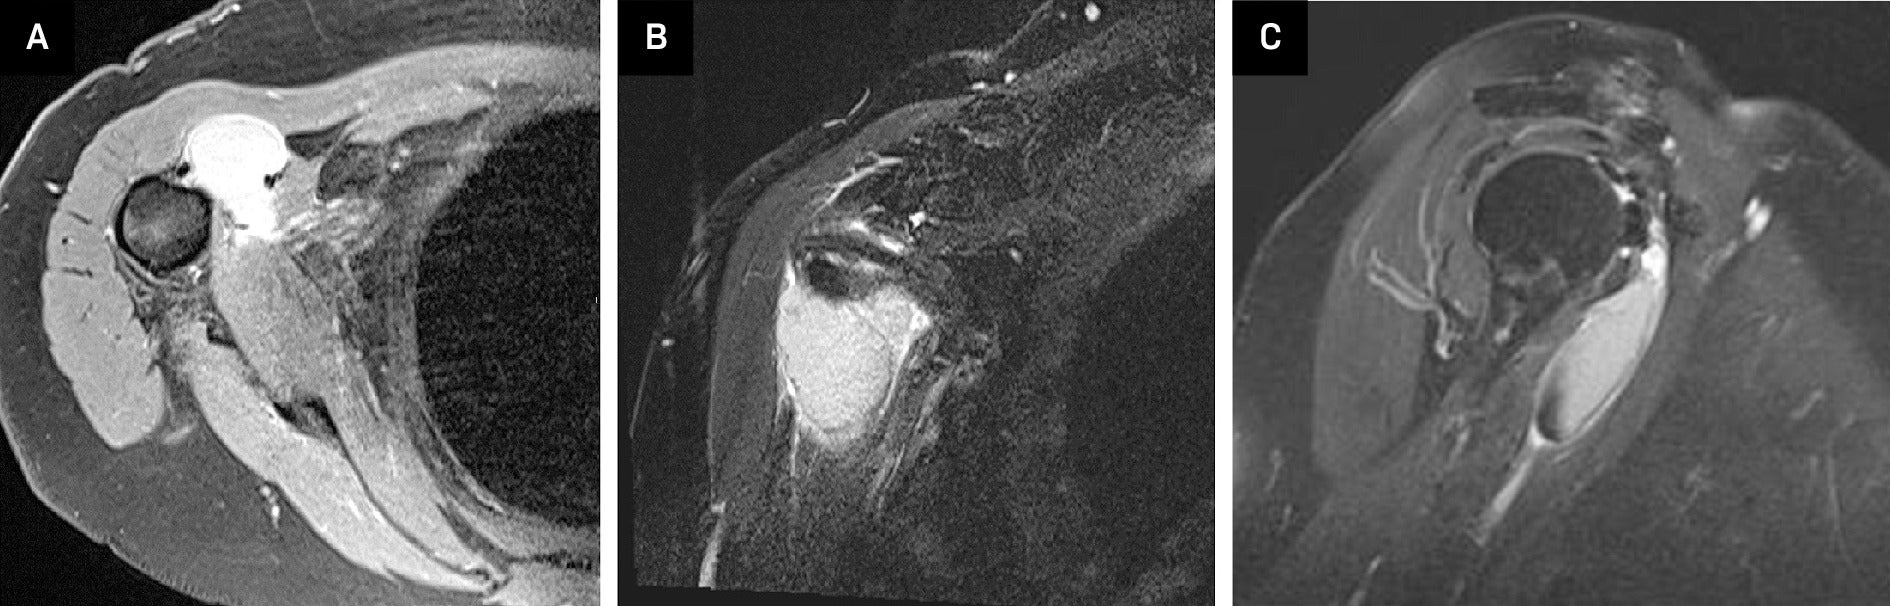

Right shoulder radiographs revealed a 2.8 × 3.4 × 1.7 cm (medial-lateral × craniocaudal × anteroposterior) calcified macro-lobulated density anterior to the humeral head in a subcoracoid position on the scapular Y view ( Figure 1 ). Notably, the calcification appeared denser in the inferior dependent portion. Non-contrast MRI depicted a uniformly mild T2 hyperintense and proton density isointense lesion, relative to skeletal muscle, with layering of hypointense material in the posteroinferior dependent portion, corresponding to the denser calcification observed on radiographs ( Figure 2 ). The lesion resided in a subcoracoid position, anterior to the subscapularis muscle, and extended between the short and long head biceps tendons, within the subcoracoid bursa. These findings were consistent with the location of the multilobulated calcified mass identified on the prior X-ray. Subsequently, an MRI with and without contrast revealed peripheral enhancement around the synovial lining of the distended subcoracoid but no internal enhancement ( Figure 3 ).

MRI shoulder without contrast: Axial view (A) of a proton density fast-spin echo sequence and a coronal view T2 fat-suppressed image (B) showed a 1.5 × 3.4 × 4.1 cm lesion which was hyperintense compared to skeletal muscle, but hypointense compared to fluid, located in a subcoracoid position. Sagittal view (C) showed a mild T2 hypointense signal along the inferior aspect of this lesion.

MRI with and without contrast: Coronal view (A) and sagittal (B) T2 fat-suppressed image without contrast again showed a hyperintense lesion within the subcoracoid bursa. A T1 axial fat-suppressed post-contrast image (C) showed peripheral enhancement around the synovial lining without internal enhancement.